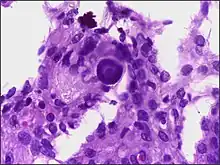

Micrograph of a meningioma showing the characteristic whorling, HPS stain

Micrograph of a psammoma body in the centre of the field in a meningioma of brain. H&E stain.

Histologically, meningioma cells are relatively uniform, with a tendency to encircle one another, forming whorls and psammoma bodies (laminated calcific concretions).[18] As such, they also have a tendency to calcify and are highly vascularized.